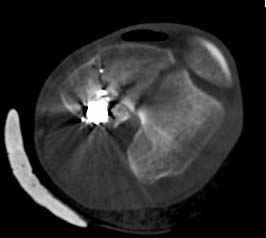

По Густило и Андерсену все high-energy переломы являются III не зависимо от степени повреждения мягких тканей. Plating такого перелома на второй день кажется немного рискованным хотя "победителей не судят". Судя по КТ, медиальный мыщелок стабильный, насколько необходимо было его фиксировать?

Идеальная репозиция?! -На снимочке A-P проeкции видна "зазубрина" по суставной поверхности, латеральный снимок - тоже не идеально.

Множество мелких FB в кости.